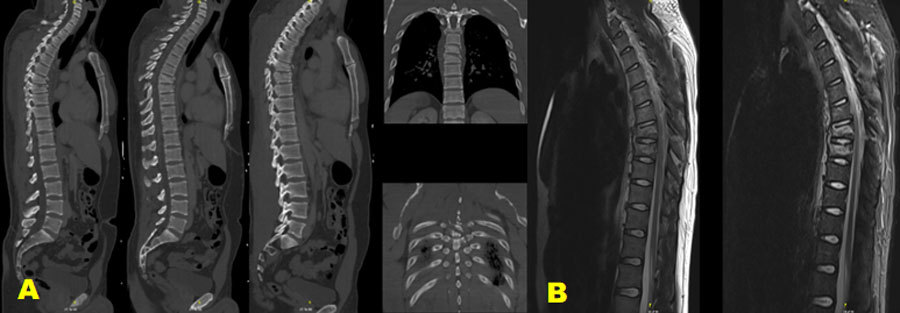

Figure 1. A 45-year-old male who was involved in a motor accident and was ejected from the vehicle. The patient was neurologically intact.

Example case 1: neurologically intact patient